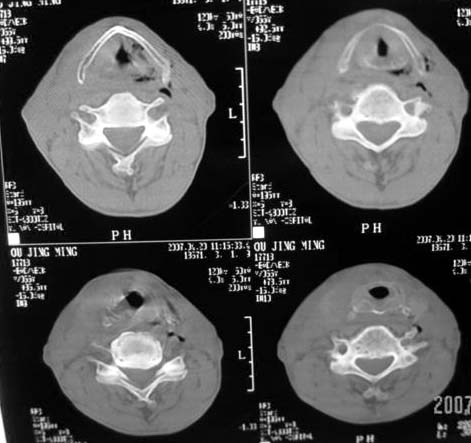

以下是引用dyqct在2007-4-20 16:19:00的发言:[br]考虑:1、左侧梨状窝区破裂伴左颈深、浅部气肿。[br] 2、右侧甲状腺区血肿(请追问病史是否伤及右颈部)。[br] 3、建议病情稳定后增强扫描除外右侧甲状腺腺瘤。